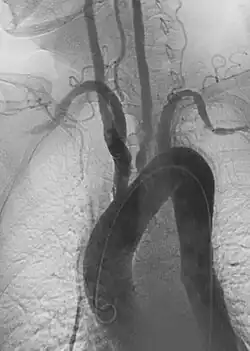

Takayasu arteritis angiography

Dissections can also arise in virtually any other artery. Carotid artery dissection, for example, places patients at increased risk for stroke and may extend further into the blood vessels within the brain. Vertebral artery dissection are less common but also dangerous for similar reasons. Mesenteric artery dissection may limit the blood supply to the intestines. Renal artery dissections can decrease blood flow to the kidneys and contribute to hypertension.[94] Peripheral arterial dissections can be found elsewhere in the arms and legs. These dissections can occur primarily due to focal traumas, underlying vascular disease, or as an extension of a larger, complex aortic dissection that tears further into these smaller branches.